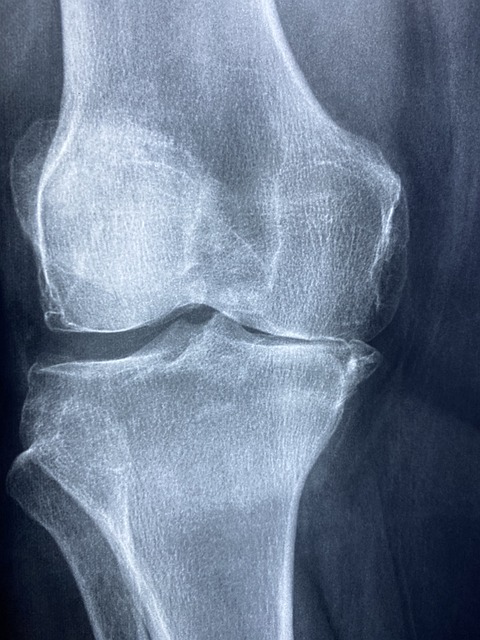

관절의 관절은 활액이라는 액체로 채워져 있으며 관절 캡슐로 싸여 있습니다. 활액은 단백질과 히알루론산을 함유한 달걀 흰자, 점성이 있는 액체로, 관절에 가해지는 마찰을 최소화하고 부드러운 움직임을 가능하게 합니다.

손가락을 당기거나 갑자기 관절을 구부리면 관절이 당겨지지만 활액의 양은 그대로 유지되기 때문에 관절낭의 압력이 단번에 떨어집니다. 그 결과 활액에서 이산화탄소와 같은 가스가 생성되고 기포가 형성됩니다.

액체는 밀봉된 상태에서 압력이 떨어지면 내부에서 가스가 생성되는 특성을 가지고 있습니다. 그런 다음 관절을 더 벌리면 이 거품이 한 번에 움직이고 터지고 무너지며 펑하는 소리를 냅니다.